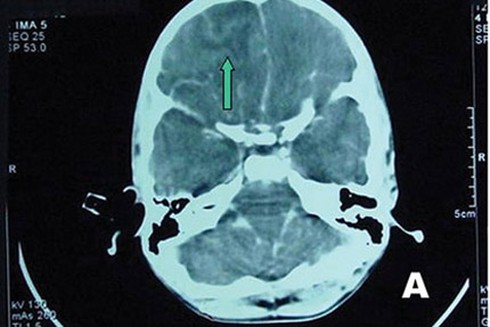

Tại BV Bệnh Nhiệt đới, BN sốt 39oC, lơ mơ, cổ cứng, thở nhanh 30 lần/phút. Kết quả xét nghiệm soi dịch não tủy không thấy có vi trùng lao hay vi nấm gây viêm màng não nhưng lại có sự hiện diện của một loại amip.

Sau đó, bệnh nhân vẫn sốt cao, 40 - 41oC, suy hô hấp, xuất huyết tiêu hóa và rơi vào tình trạng hôn mê sâu. Đến 23g ngày 31/7, BN nhiều lần bị ngưng tim đột ngột, tử vong.

Sau khi anh T. tử vong, BV Bệnh Nhiệt đới tiếp tục làm nhiều xét nghiệm và kết quả xét nghiệm sinh học phân tử PCR cho thấy anh tử vong do “amip ăn não người” tấn công.